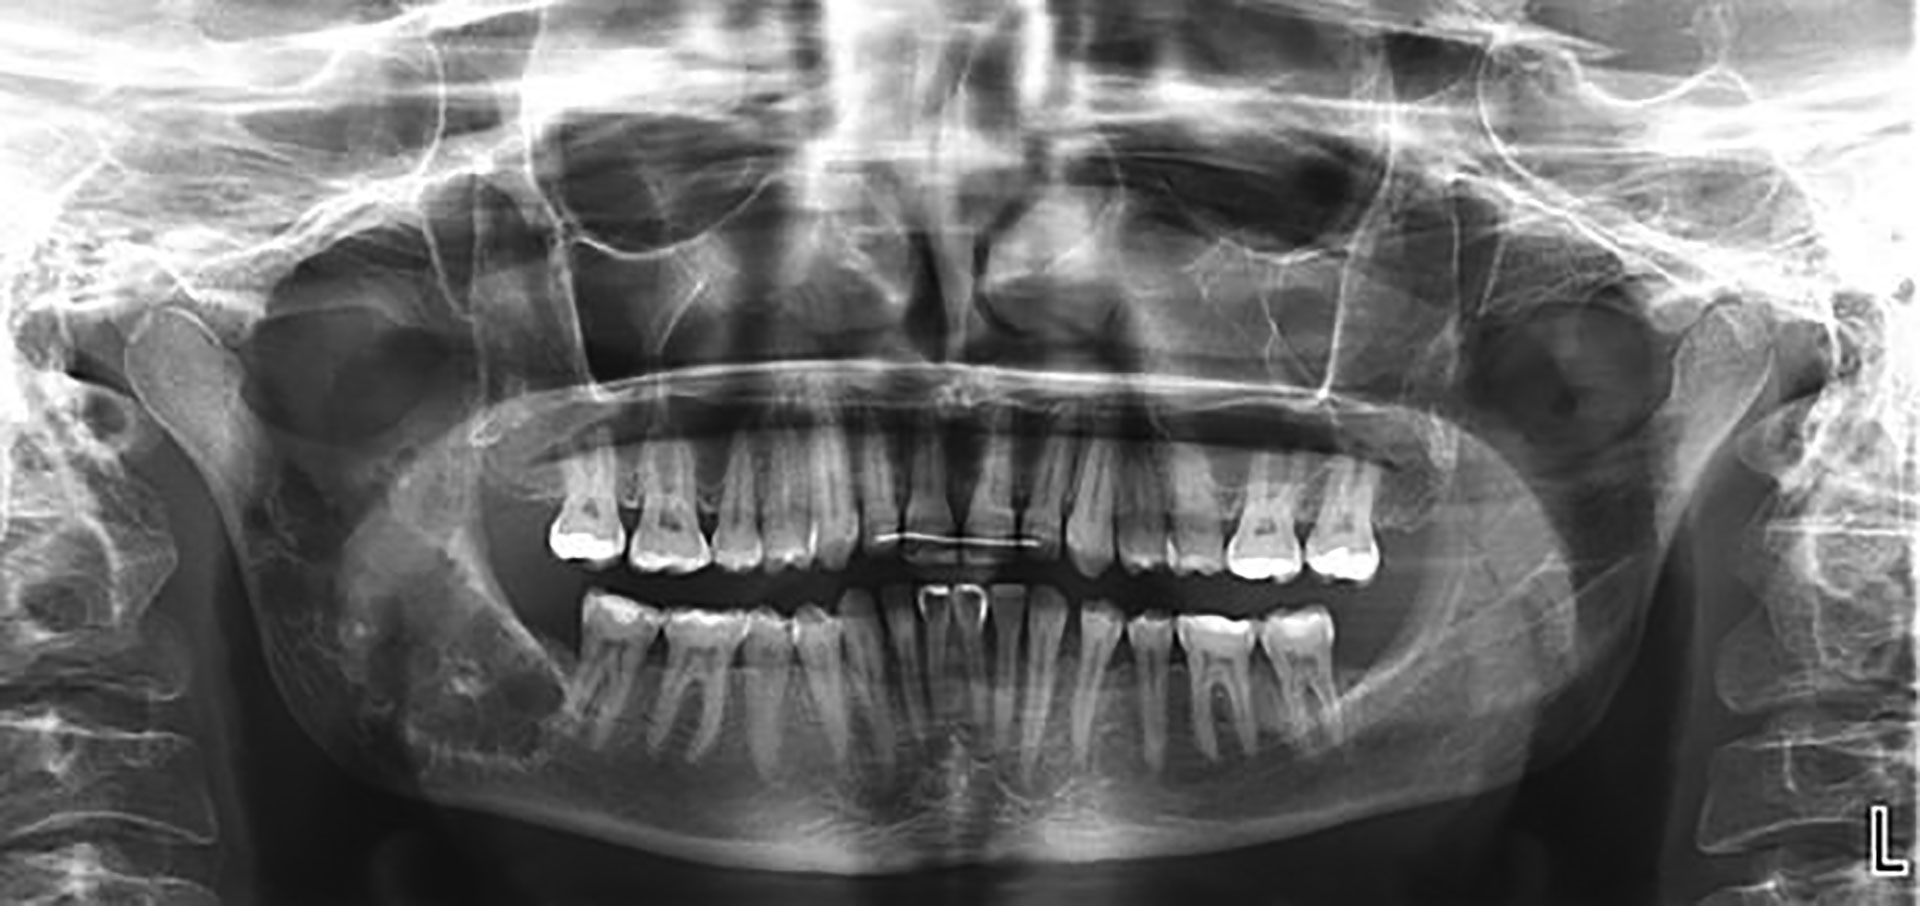

På OPG fra henvisende tannlege så man i store deler av ramus mandibula en oval radiolusens ispedd opake partier (figur 1). I forandringens periferi var det en diffus sklerotisk sone. Bildene ble supplert med et nytt OPG og CBCT.

Figur 1 OPG viser multicystisk oppklaring utfyllende det meste av høyre ramus mandibula frem til tann 47.